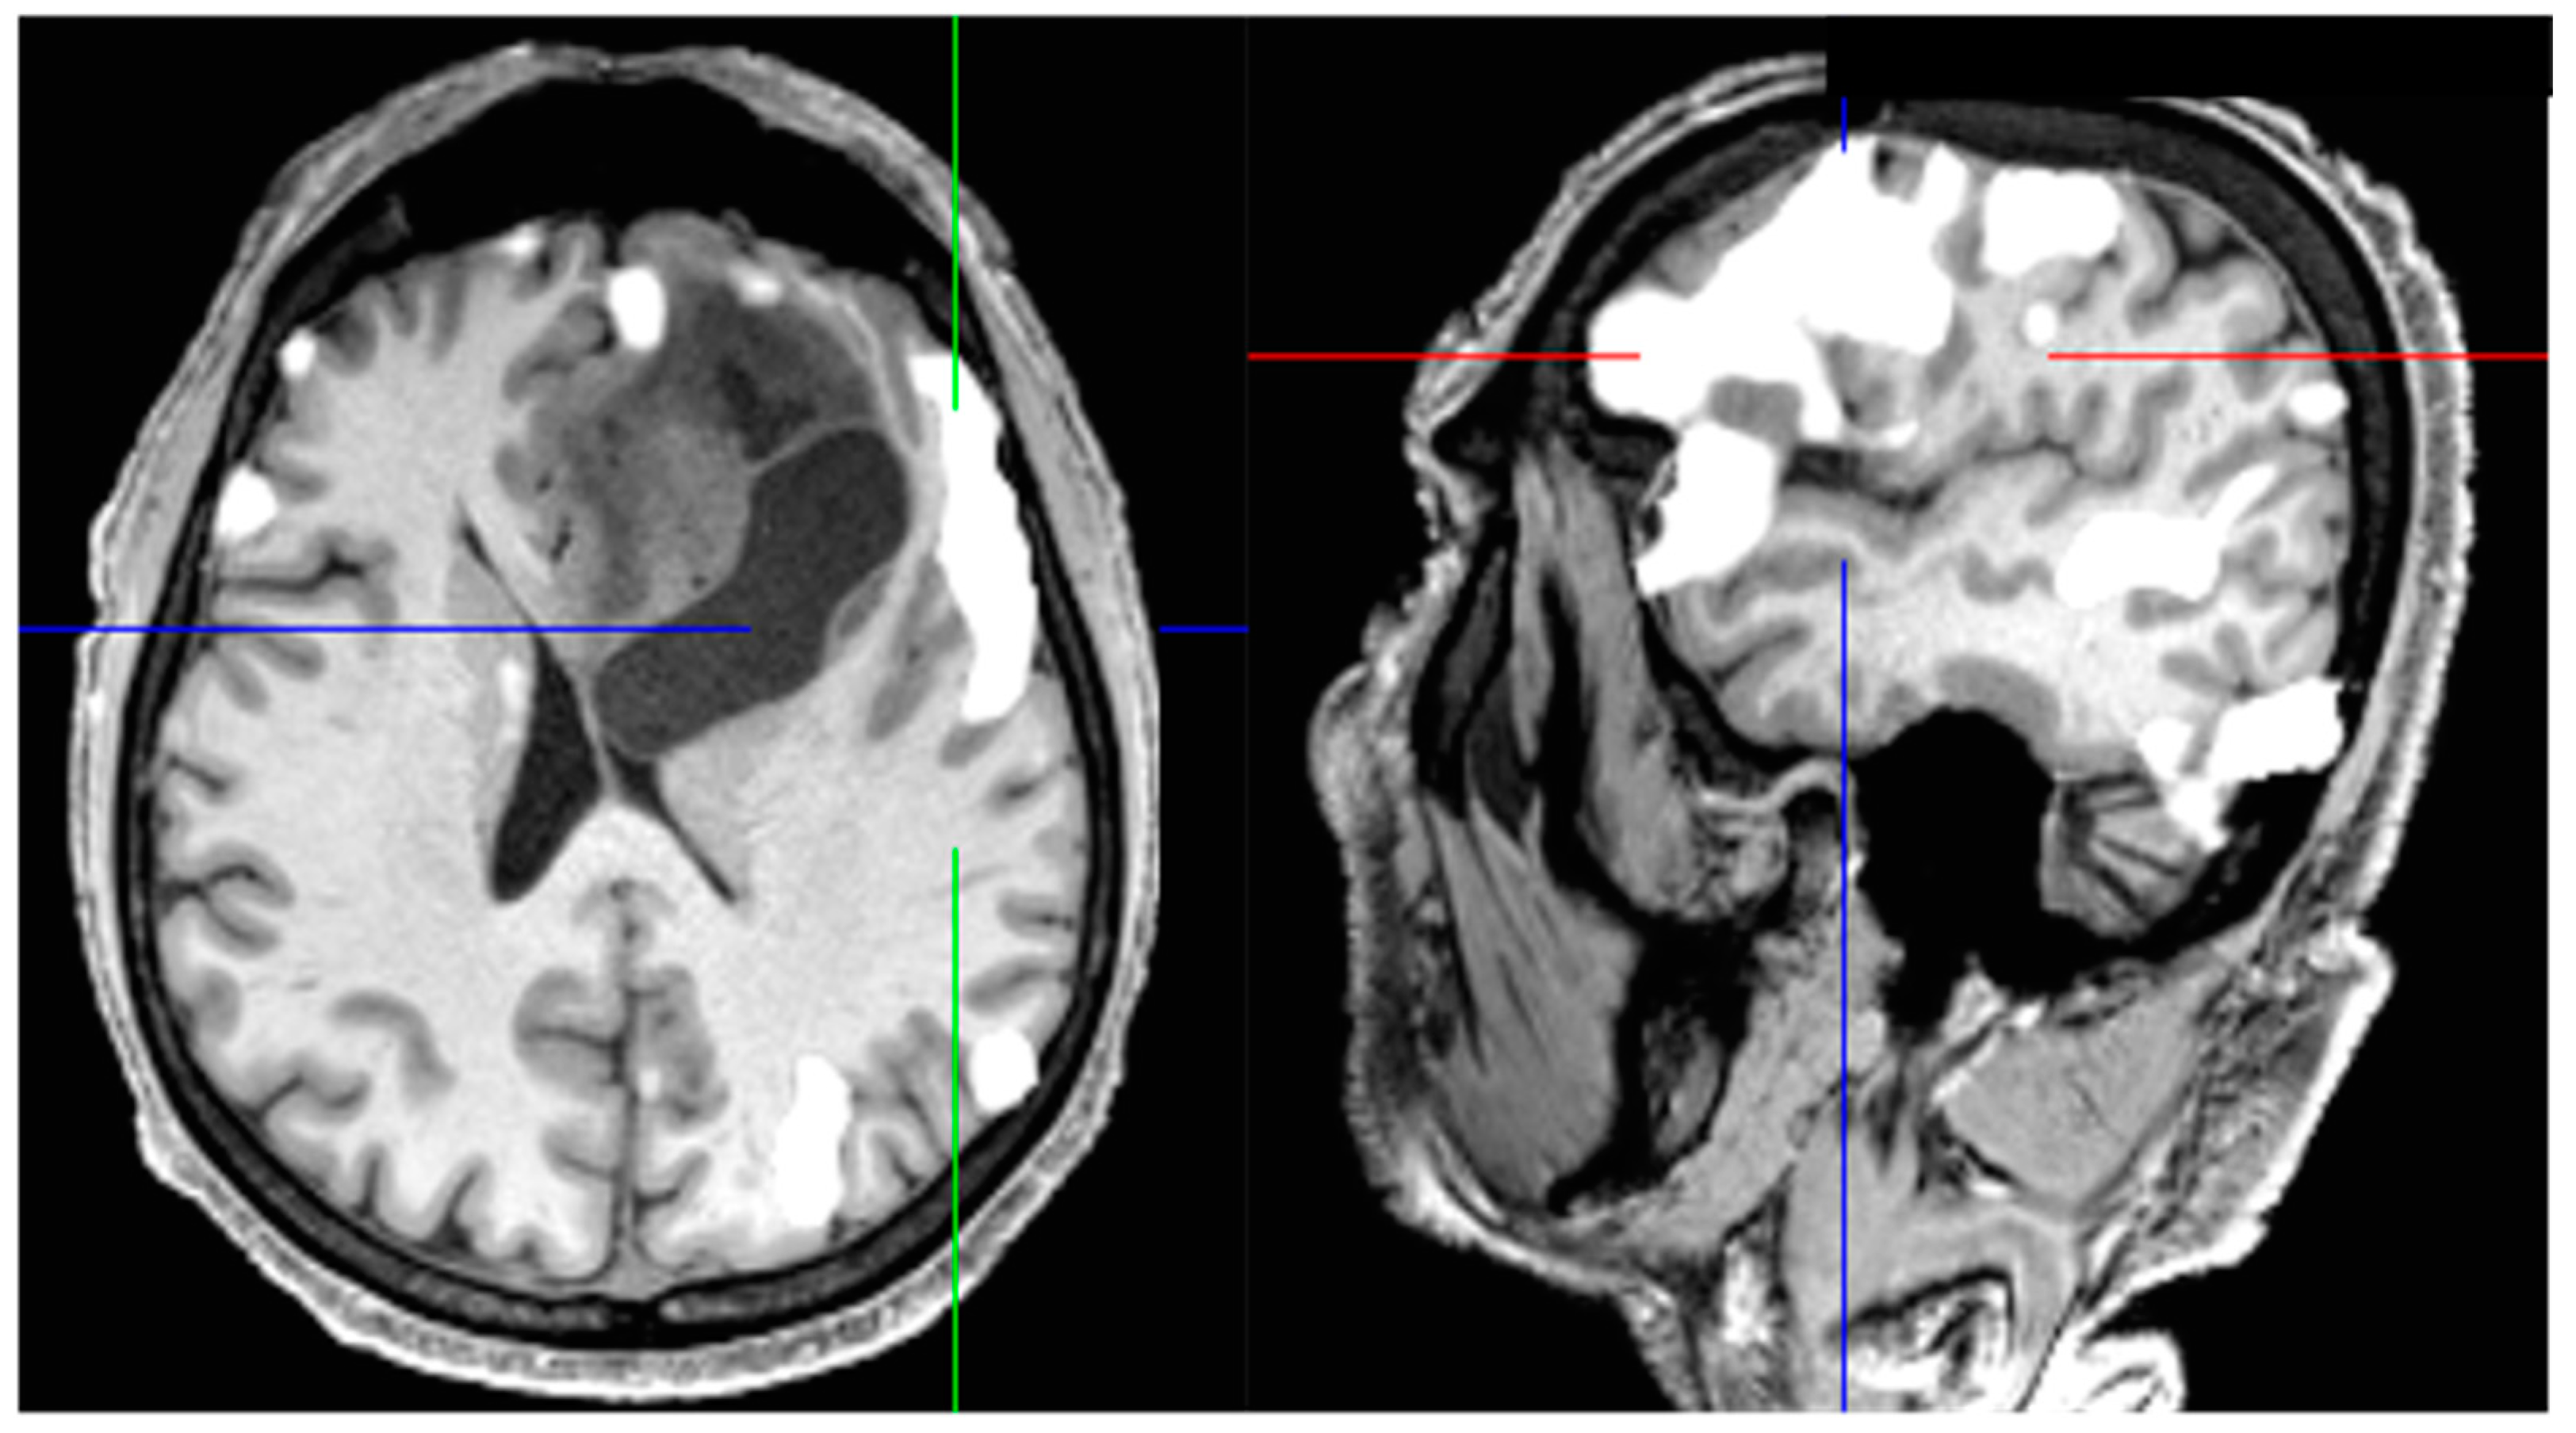

- Abdullah, K.G.; Lubelski, D.; Nucifora, P.G.P.; Brem, S. Use of diffusion tensor imaging in glioma resection. Neurosurg. Focus 2013, 34, E1. [Google Scholar] [CrossRef] [PubMed] [Green Version]

- Bello, L.; Gambini, A.; Castellano, A.; Carrabba, G.; Acerbi, F.; Fava, E.; Giussani, C.; Cadioli, M.; Blasi, V.; Casarotti, A.; et al. Motor and language DTI Fiber Tracking combined with intraoperative subcortical mapping for surgical removal of gliomas. NeuroImage 2008, 39, 369–382. [Google Scholar] [CrossRef]

- Stadlbauer, A.; Nimsky, C.; Gruber, S.; Moser, E.; Hammen, T.; Engelhorn, T.; Buchfelder, M.; Ganslandta, O. Changes in Fiber Integrity, Diffusivity, and Metabolism of the Pyramidal Tract Adjacent to Gliomas: A Quantitative Diffusion Tensor Fiber Tracking and MR Spectroscopic Imaging Study. AJNR Am. J. Neuroradiol. 2007, 28, 462–469. [Google Scholar]

- Nimsky, C.; Ganslandt, O.; Merhof, D.; Sorensen, A.G.; Fahlbusch, R. Intraoperative visualization of the pyramidal tract by diffusion-tensor-imaging-based fiber tracking. NeuroImage 2006, 30, 1219–1229. [Google Scholar] [CrossRef]

- Stadlbauer, A.; Nimsky, C.; Buslei, R.; Salomonowitz, E.; Hammen, T.; Buchfelder, M.; Moser, E.; Ernst-Stecken, A.; Ganslandt, O. Diffusion tensor imaging and optimized fiber tracking in glioma patients: Histopathologic evaluation of tumor-invaded white matter structures. NeuroImage 2007, 34, 949–956. [Google Scholar] [CrossRef]

- Raffa, G.; Bährend, I.; Schneider, H.; Faust, K.; Germanò, A.; Vajkoczy, P.; Picht, T. A Novel Technique for Region and Linguistic Specific nTMS-based DTI Fiber Tracking of Language Pathways in Brain Tumor Patients. Front. Neurosci. 2016, 10, 552. [Google Scholar] [CrossRef]

- Romano, A.; D’Andrea, G.; Minniti, G.; Mastronardi, L.; Ferrante, L.; Fantozzi, L.M.; Bozzao, A. Pre-surgical planning and MR-tractography utility in brain tumour resection. Eur. Radiol. 2009, 19, 2798–2808. [Google Scholar] [CrossRef]

- Sollmann, N.; Kelm, A.; Ille, S.; Schröder, A.; Zimmer, C.; Ringel, F.; Meyer, B.; Krieg, S.M. Setup presentation and clinical outcome analysis of treating highly language-eloquent gliomas via preoperative navigated transcranial magnetic stimulation and tractography. Neurosurg. Focus 2018, 44, E2. [Google Scholar] [CrossRef]